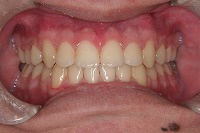

18歳1か月

正面

反対咬合と下顎が出ている事を主訴に来院された、初診時18歳1か月の男性です。診断「上顎骨の後方位による骨格性反対咬合」非抜歯での矯正治療と、下顎を後退させる外科手術を併用して治療を行いました。